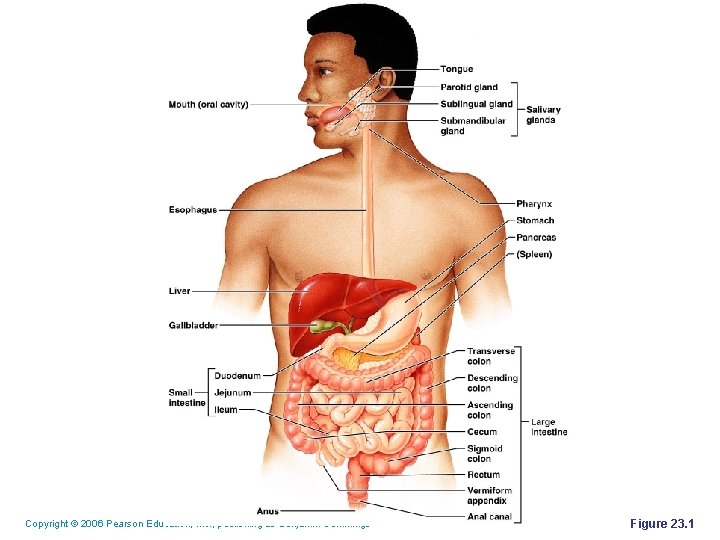

Copyright © 2006 Pearson Education, Inc. , publishing as Benjamin Cummings Figure 23. 1

Digestive System Brainstorm what each of the following organs/structures does regarding digestion: § § § The alimentary canal or gastrointestinal (GI) tract digests and absorbs food Alimentary canal consists of – mouth, pharynx, esophagus, stomach, small intestine, and large intestine Accessory digestive organs – teeth, tongue, salivary glands, liver, gallbladder and pancreas Copyright © 2006 Pearson Education, Inc. , publishing as Benjamin Cummings